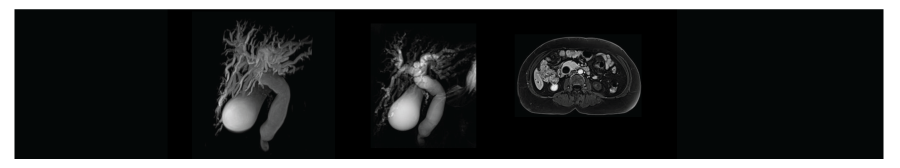

การตรวจระบบช่องท้องและระบบทางเดินอาหาร

การตรวจ MRCP (Magnetic Resonance Cholangiopancreatography) คือ การวินิจฉัยและประเมินความผิดปกติของระบบทางเดินน้ำดีและตับอ่อน ข้อดี คือ ไม่ต้องฉีดสารทึบรังสี (ในบางกรณีจำเป็นต้องฉีด) และไม่ก่อให้เกิดการรุกรานร่างกาย (ไม่เจ็บปวด) ทำให้มีความปลอดภัยและลดความเสี่ยงต่อการแพ้หรือผลข้างเคียงจากสารทึบรังสี นอกจากนี้ MRCP ยังให้ภาพที่มีความละเอียดสูง ช่วยให้แพทย์สามารถมองเห็นรายละเอียดของท่อทางเดินน้ำดีและท่อตับอ่อนได้อย่างชัดเจน ช่วยในการวินิจฉัยโรคต่างๆ เช่น นิ่วในท่อทางเดินน้ำดี, การอุดตันของท่อทางเดินน้ำดี, เนื้องอก หรือการอักเสบ เป็นต้น